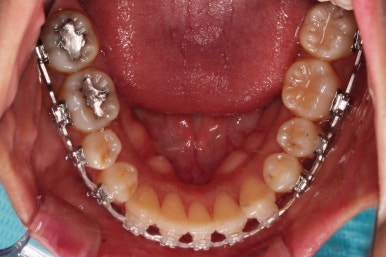

아랫니는 최대한 추가 발치 없이 후방의 송곳니를 당겨와서 앞니 역할을 하게 했습니다.(총 4개 앞니처럼)

중앙선, 교합, 앞니 맞물림 등 모든 것이 좋아졌네요.

교합, 정중선 모두 좋아졌고요.